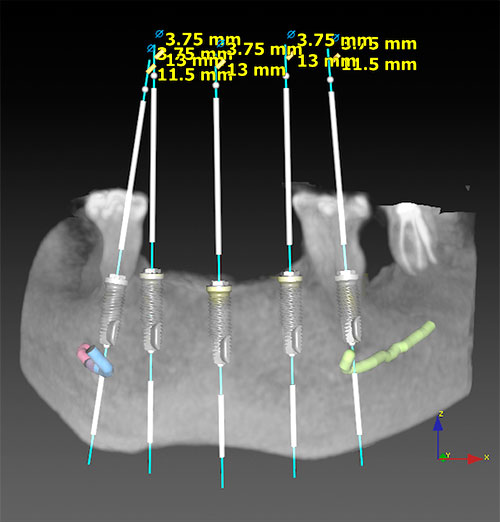

La tomografía computerizada de haz cónico (CBCT) se ha erigido en un medio diagnóstico de incalculable valor para nuestra profesión. Se ha logrado minimizar la exposición del paciente, comparado con los antiguos escáneres (TC) de uso en medicina, y además se ha conseguido una exactitud de reproducción, indispensable a la hora de planificar nuestras intervenciones. La calidad de las imágenes nos ayudan a diagnosticar múltiples patologías y su campo de aplicación se extiende a especialidades tan diferentes entre sí como la implantología, cirugía oral, ortodoncia, endodoncia, etc.

El paciente podrá ver con suma facilidad una imagen en tres dimensiones de su mandíbula o maxilar, entendiendo perfectamente el alcance de su patología o la planificación del tratamiento que le propone el doctor.